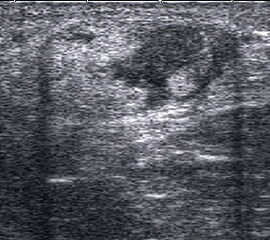

Fibulafraktur mit Unterbrechung der Kortikalis und Hämatom.

Abbildung 13

Lagerung: Rückenlage, leichte Innrotation des Fußes.

Schnittebene: LS über distaler Fibula.

Referenzstruktur: Fibula im Längsverlauf.

Befunde: Bei einer Außenknöchelfraktur ist eine Unterbrechung der echogenen metaphysären Knochenlinie mit umgebendem flachen, echoarmen periostalen Hämatom zu sehen (Abb.13).

Cave: Ein Os subfibulare kann ebenfalls fälschlicherweise als Fibulaverletzung interpretiert werden!